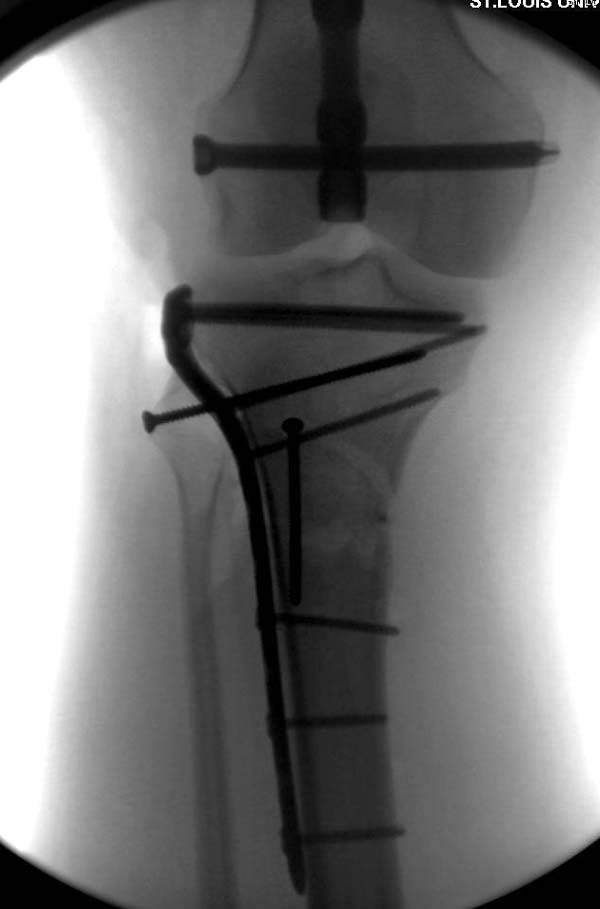

Здесь, кроме перелома верхней трети голени, имеется вовлечение сустава, и, чтобы не пропустить смещение суставной поверхности, надо делать КТ. Срезы КТ покажут о необходимости субхондральной фиксации, которая проводится 3.5 мм параллельными шурупами (Raft technique). Не имеет значения, как проводить: отдельно субхондрально или через верхний ряд пластины. Главная задача фиксации удержать суставную поверхность от коллапса в вальгус или варус.

здравствуйте! создается впечатление о фиксации перелома голени в варусном положении

Согласен, на снимке “создается впечатление о фиксации перелома голени в варусном положении”, но на других отсутствует..